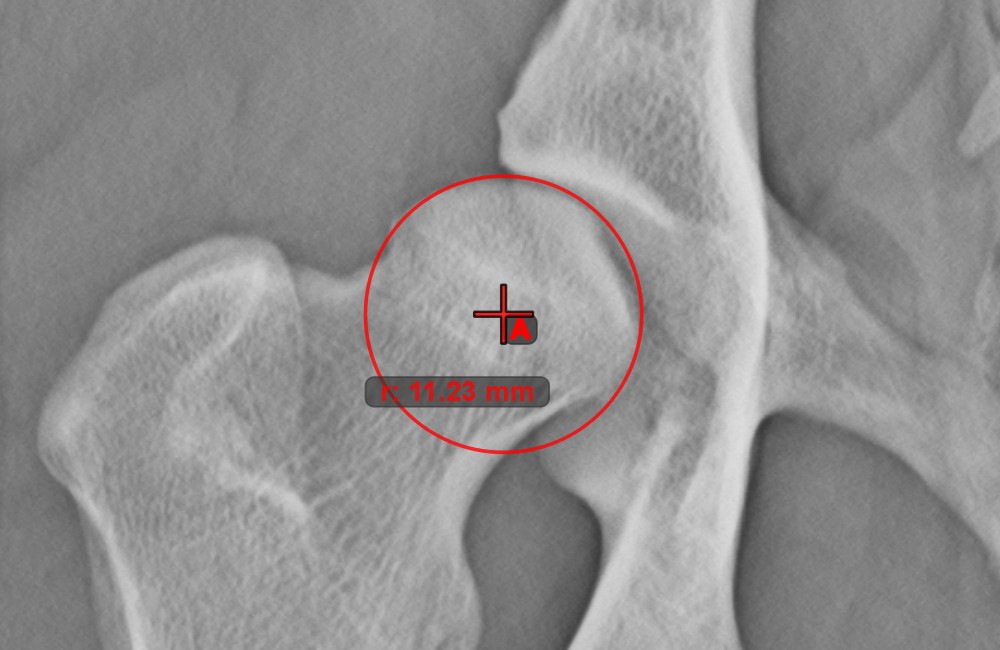

Circle with Defined Radius¶

Draw a circle with fixed radius by using the Circle with Defined Radius

tool. Only the position of the circle on the scene can be modified later.

Select the tool from the left toolbar and assign it to one of the available mouse buttons. Place the origo of the new circle on the scene or select an already existing point. Specify the desired radius of the circle and press OK

to complete the measurement.